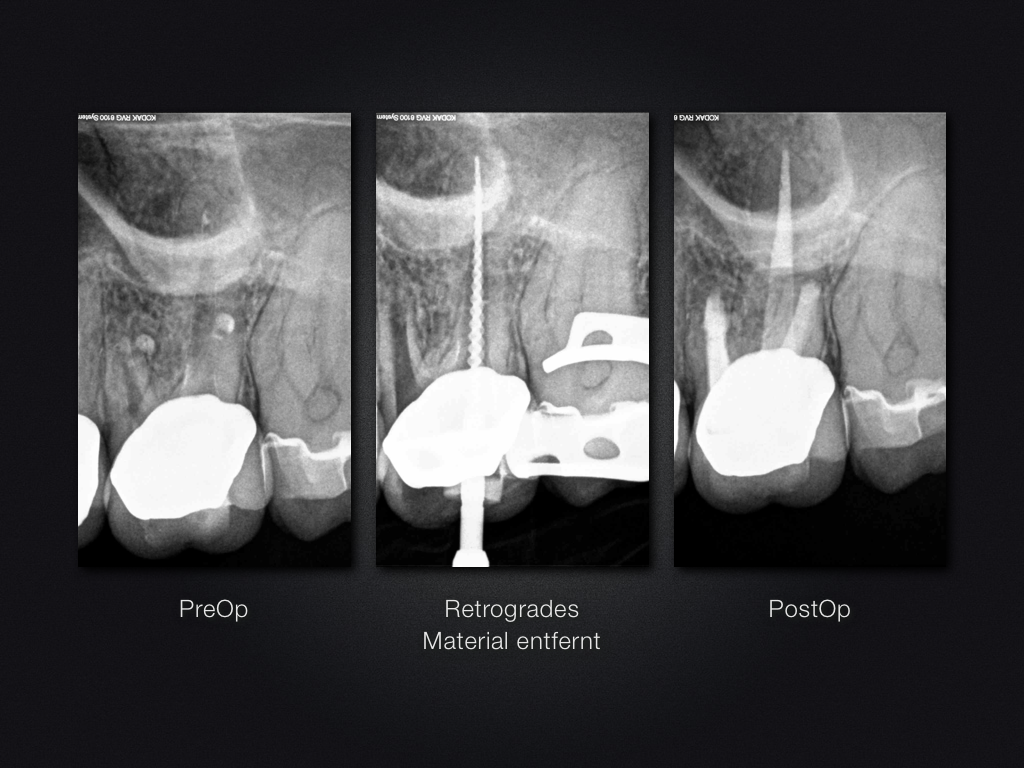

Saving Hopeless Teeth (XXXII)